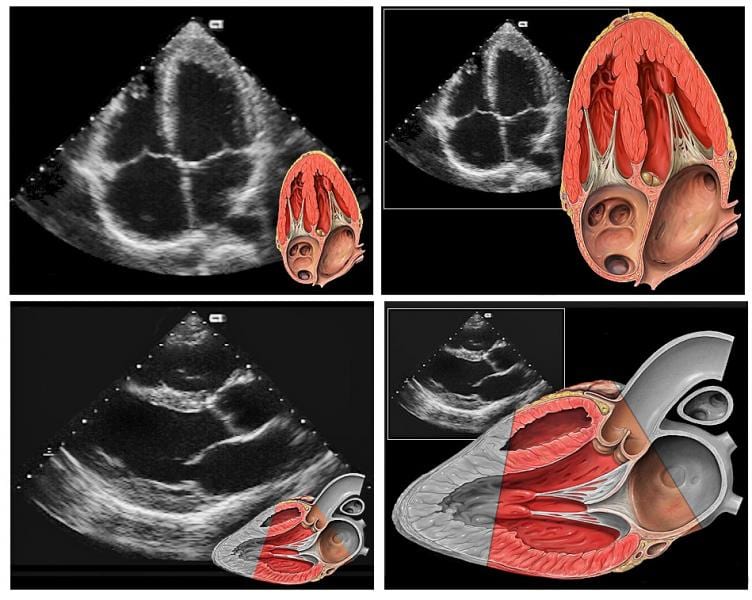

С помощью ультразвука, отраженного от различных кардиальных структур, доктор подробно анализирует состояние клапанного аппарата, сердечной мышцы (миокарда), камер сердца и отходящих от него крупных сосудов (аорта, легочная артерия).

Метод ЭХОКГ дает возможность диагностировать следующие заболевания и состояния: